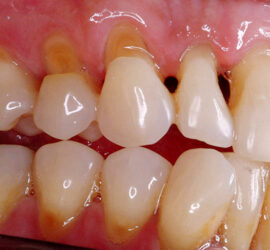

Аномалии строения и пороки развития зубов Пороки тканей зуба многообразны, они могут проявляться изолированно и сочетаться с аномалиями строения и пороками развития органов и систем всего детского организма, в том числе челюстно-лицевой области. Ткани зуба имеют эктодермальное (эмаль) и мезодермальное (дентин, пульпа, цемент) происхождение. В связи с этим пороки эмали […]